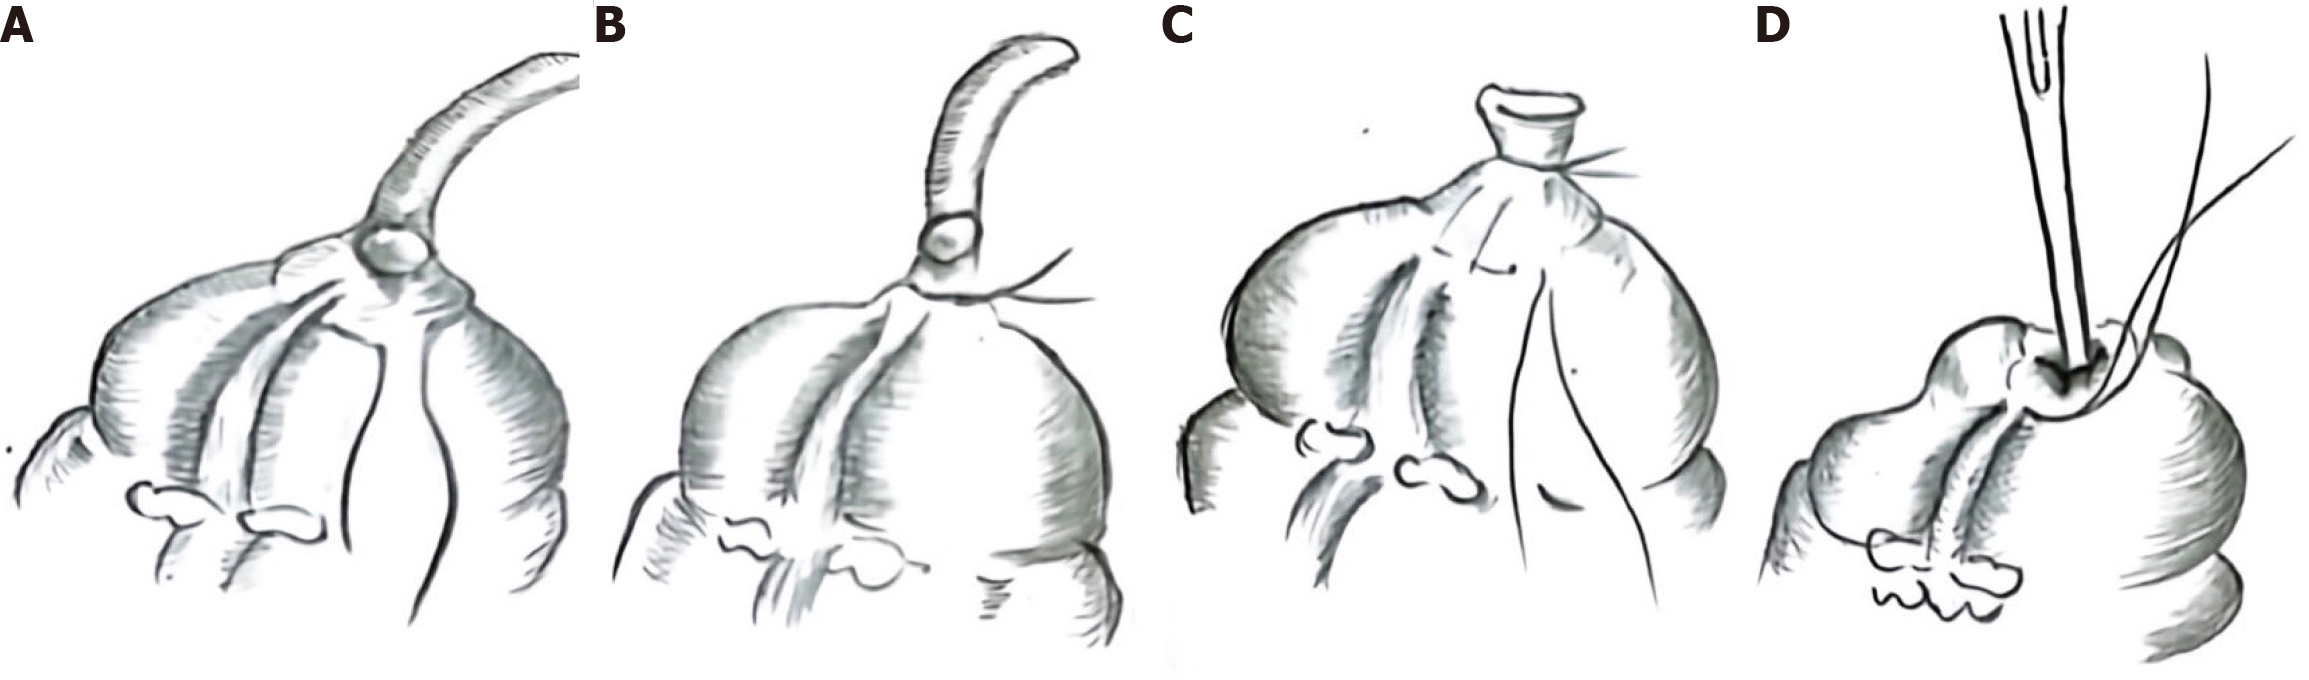

Before surgery, we communicated with the patient’s family regarding the surgical methods, including the double purse-bag method and the double purse-bag method. Due to the cost of surgery, the patient’s family chose the double purse-bag method. Laparoscopic surgery was performed on May 21, 2022. The patient received bowel preparation prior to the planned surgery. Absorbable surgical sutures, model 3-0, were used throughout surgery. During the operation, we did not find any surface mucin or mucin in the right iliac fossa or Morrison’s pouch. The double purse-string suture technique was performed by creating a purse-string suture approximately 1.0 cm below the swelling, at the appendiceal orifice. The incision was made 0.5 cm from the ligature line, and the appendix and swelling at the orifice were completely excised (Figure 2A and B), and a second purse-string suture was performed 1.0 cm from the ligature line, with the remaining end embedded and sutured into the purse (Figure 2C and D).

Most studies have shown that LAMNs that are confined to the appendix, without perforation or peritoneal metastasis, can be cured with a simple appendectomy, which has a low recurrence rate[4]. For LAMNs with mass formation at the appendiceal orifice, if no metastatic lesion is indicated by imaging, the appendix and the mass at the appendiceal orifice should be completely resected. Anatomically, the ileocecal valve is located 2.0-3.0 cm from the opening of the appendix, and our technique mainly targeted a mass approximately 1 cm from the opening of the appendix. We made the first pouch 1 cm from the root of the appendix, thus ensuring the anatomical integrity of the ileocecal valve. If a conventional cutting closure is used, the anatomy of the ileocecal flap may be destroyed. If only the appendix is resected, there is a high probability of positive resection margins. For patients with positive resection margins, some guidelines currently recommend additional procedures, such as a typhlectomy, ileocecal resection or right hemicolectomy[5,6].